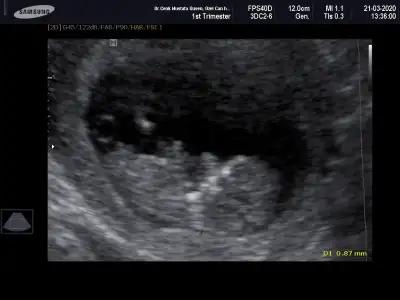

Merhabalar, ctesi ikili test icin gittim 11+6 idim. Suana kadar hep haftayla uyumlu giderdi sat. Ama bu sefer 12+6 cıktım. Yine de cinsiyet yorumlar mısınız? Gec mi kaldım? Bir de doktor tahminini söyledi ama emin değil. Kafanız karışmasın diye en son söyleyeceğim.

Bir de bunu verdi doktor. Sanırım bacak arası ve kenardakiler de bacakları burada. 11+6 idim.